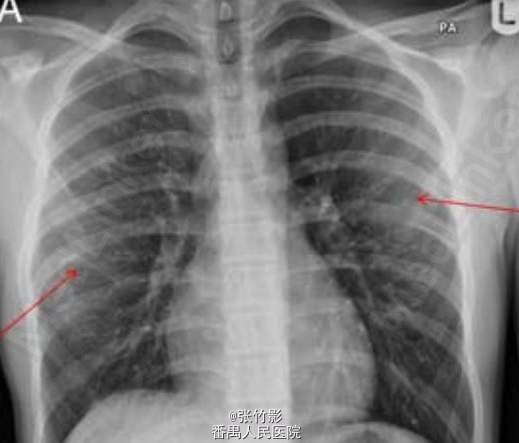

主诉:右侧胸痛、咳嗽伴间歇性发热 2 周。 病史:14岁男童,2周前无明显诱因出现右侧胸部疼痛,咳嗽,少量咳痰,为黄色粘液痰。伴有间歇性发热,最高可达38.1℃。于门诊查胸部X线未见明显异常,就诊后嘱托患者若症状无缓解则需再次返院就诊。1 周后患者再次就诊,呼吸费力、胸痛、体温最高达 38.5℃。患者精神状态较差,睡眠差,胃纳差,体重无明显变化。

查体:右侧胸部叩诊浊音,呼吸音减弱;未问及明显干湿性啰音。 辅查:首次就诊血液学检查白细胞计数正常,C 反应蛋白升高(303 mg/L);两次胸部X线如下。

诊断:骨性肋外生骨疣引起血胸。 处理:患儿呼吸急促,需要吸氧 1-2L/min,同时对患者静脉用克拉维酸和克拉霉素。在超声介导下行右半胸腔穿刺引流,引流出 750 ml 深黑色的血性液体,而非脓液。